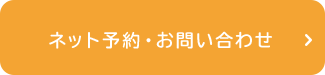

初診時の口腔内

診査の結果、金具をかけている歯がむし歯になっているため(写真黃丸)、金具のバネ(クラスプ)がしっかりと歯にかかっておらず、入れ歯が浮きやすい状態になっていました。入れ歯が浮いてしまうと、食べ物が挟まり、痛みが出てしまいます。また、入れ歯が動いてしまうので、話もしにくくなります。さらに、入れ歯が沈み込まないようにする装置(レスト)も歯に合っておらず(写真青丸)、入れ歯が過度に沈み込み、歯ぐきを傷めていました。